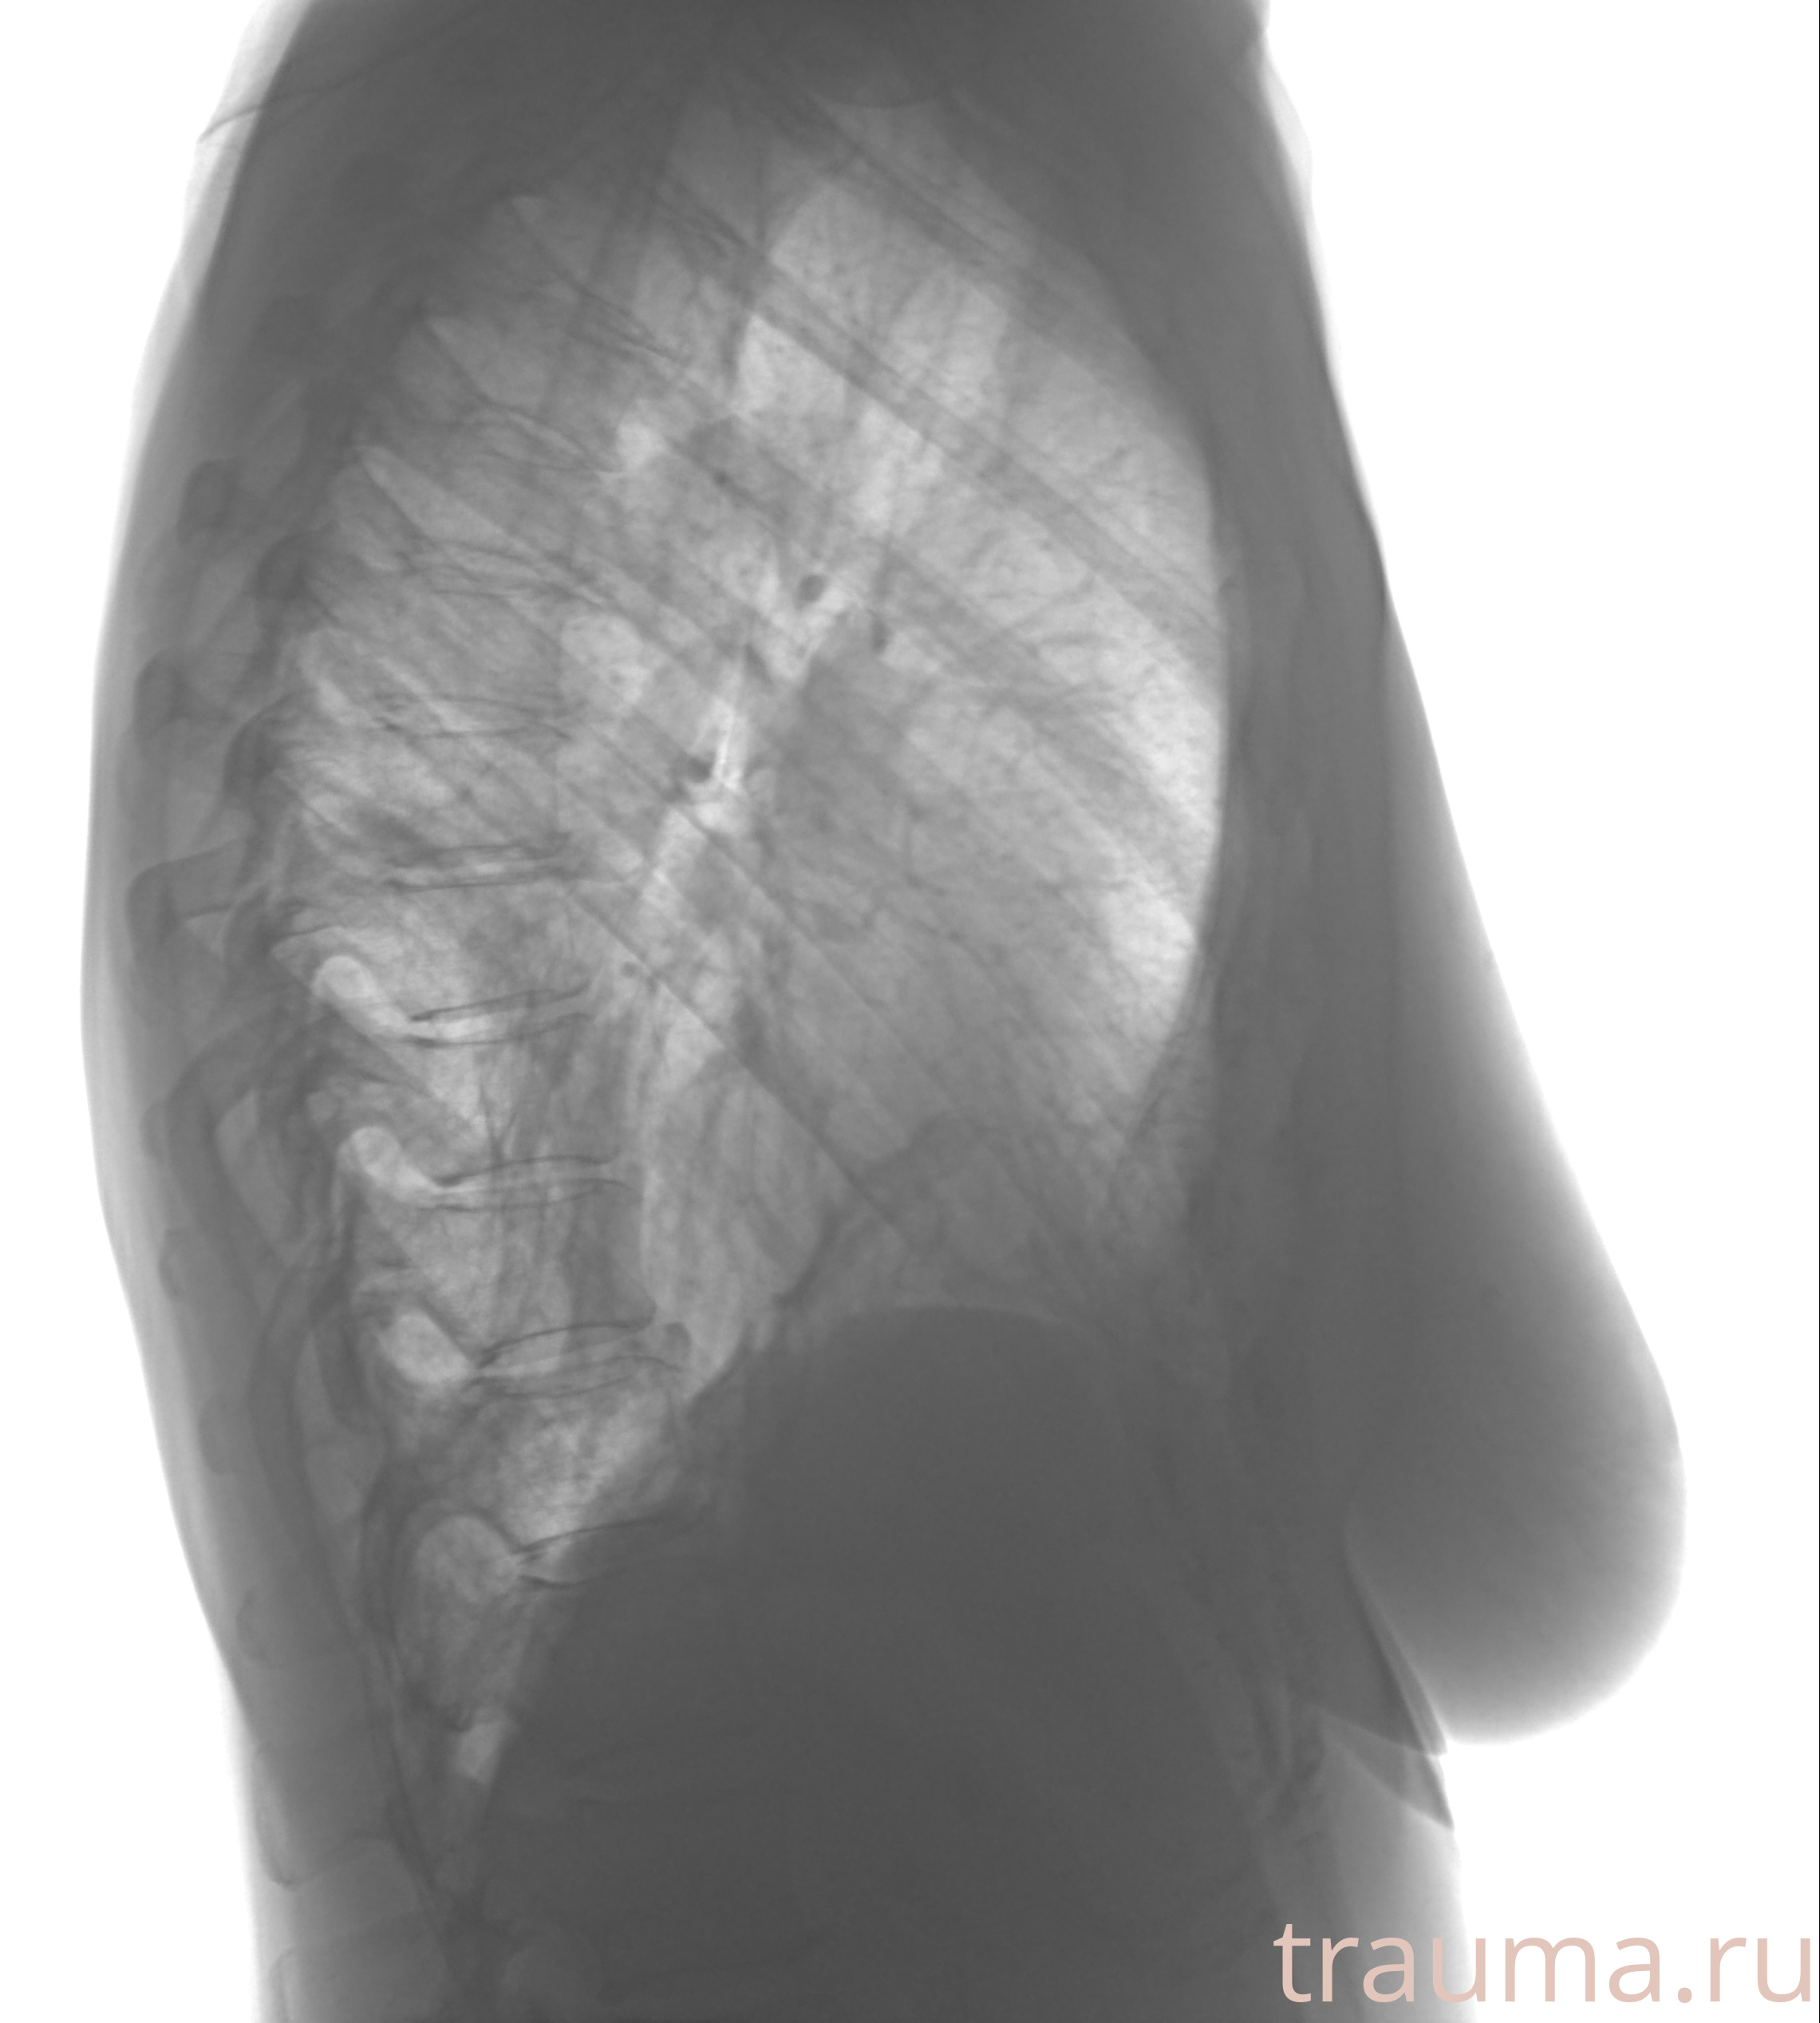

Рентгенограммы

Рентген на дому: по вашему адресу приезжает врач-рентгенолог, травматолог-ортопед с мобильным рентгеновским аппаратом, проводит диагностику травмы или заболевания, делает необходимые рентгенограммы, дает рекомендации по дальнейшему лечению. Получить качественные снимки в домашних условиях возможно благодаря уникальной методике, разработанной МосРентген Центром для института  Склифосовского

Яркость: 1   Контраст: 1   Инвертировать: 0 Увеличение: 1

Перетаскивайте мышь вверх/вниз для контраста, влево/право для яркости. Прокрутка колесом изменяет масштаб. Нажмите Сбросить для возврата к исходному изображению. При увеличении держите мышь в той области, которую хотите рассмотреть.